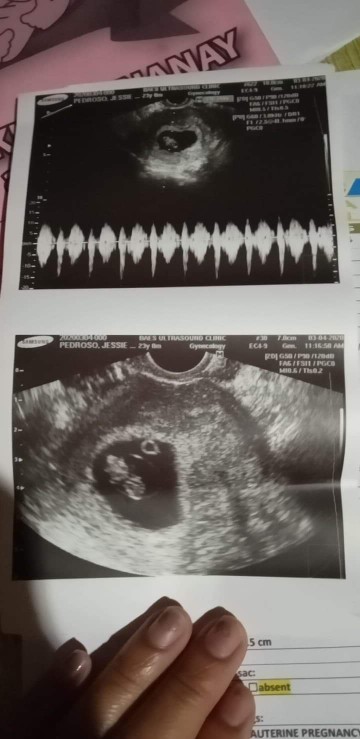

positive po ba ito or negative? please po paki sagot naman

Positive po siya. Early stage